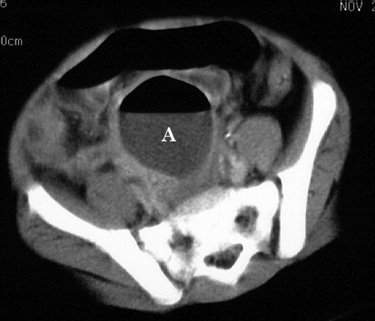

| Perforated appendicitis mimicking small bowel

obstruction. 4 year old girl presented with a four day history of anorexia, nausea, and vomiting. Physical examination was significant for pain on rectal examination. Plain films, a barium enema, and CT examination were obtained, shown below. |

|  | Figure 4. Contrast-enhanced CT image of the mid-pelvis shows a midline gas and fluid collection (A) consistent with an abscess. The appendix is not visible. |